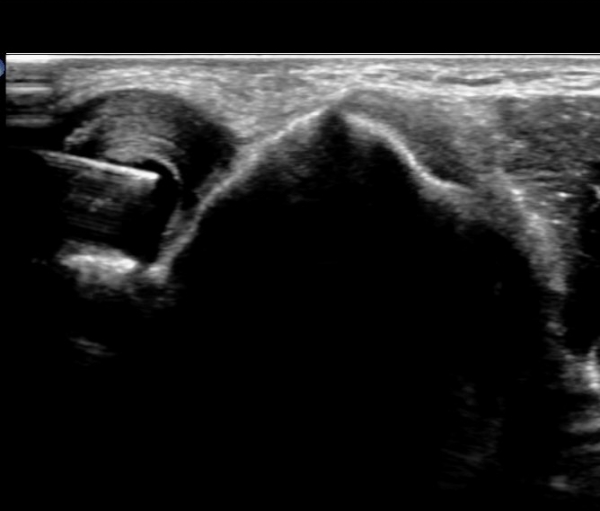

ÆÈ²ÞÄ¡ µÚÂÊ Á¾´Ü¸é°Ë»ç¿Í Ⱦ´Ü¸é°Ë»ç¿¡¼­ ÁֵοÍ(olecranon fossa)¿¡ ¼ö¾×Àú·ù°¡ °üÂûµÊ(»çÁø 1, 2)

Áֵοͳ» ÁÖ»çÄ¡·á¸¦ À§ÇØ È¯ÀÚ¸¦ ¿·À¸·Î ´¯°ÔÇÏ°í ÆÈ²ÞÄ¡¸¦ Æí »óÅ¿¡¼­ ¸ö ¿·¿¡ ÆÈÀ» ´ë°í ŽÃËÀÚ¸¦

ÁֵοͿ¡ ȾÀ¸·Î ´í »óÅ¿¡¼­ ¼ö¾×Àú·ù°¡ °¡Àå Àß º¸ÀÌ°í ¼ö¾× Àú·ù¿¡ Áֻ簡 °¡´ÉÇÑ À§Ä¡¿¡¼­

¼ö¾×Àú·ù¸¦ È®ÀÎÇÑ´Ù(»çÁø 6)